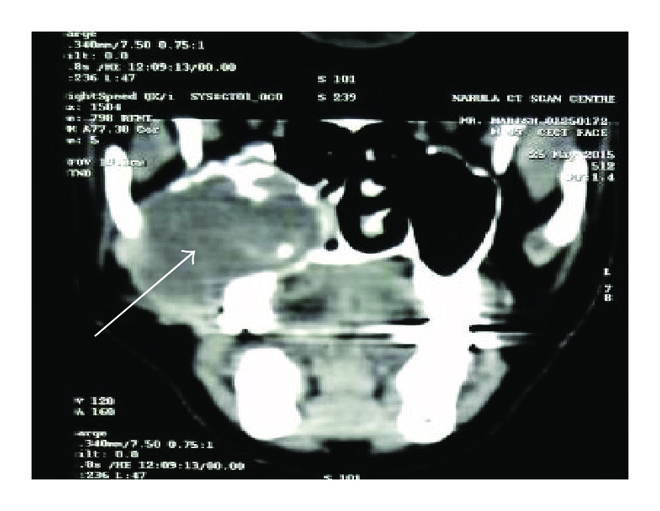

2.3. Case 3

A 47-year-old male reported with complaint of pain in lower left posterior mandible for past two days. He gave history of swelling on this side since two months. Mild swelling was present on left side of mandible, which was hard on palpation and nontender. Intraorally the swelling was soft in consistency and painful with a slight opening present on crest region through which yellowish green color discharge was noticed. Computed tomography revealed a well-defined radiolucency (30 × 14 mm in size) present on left angle of mandible region with 38 displaced near the inferior border of the mandible. Incisional biopsy was sent for histopathological evaluation which revealed cystic lining of varying thickness, nonkeratinized stratified squamous in nature with few areas of mucus metaplasia. Connective tissue capsule was fibrocellular with vascular channels and mild inflammatory cell infiltrate and a diagnosis of dentigerous cyst was made. After this the excised tissue was sent which after repeated regrossing and tissue sectioning did not show any cystic lining. The connective tissue stroma was ectomesenchymal and fibrocellular with abundant cholesterol clefts and chronic inflammatory cell infiltrate (Figure 3).

(a)

(b)

(c)

(d)